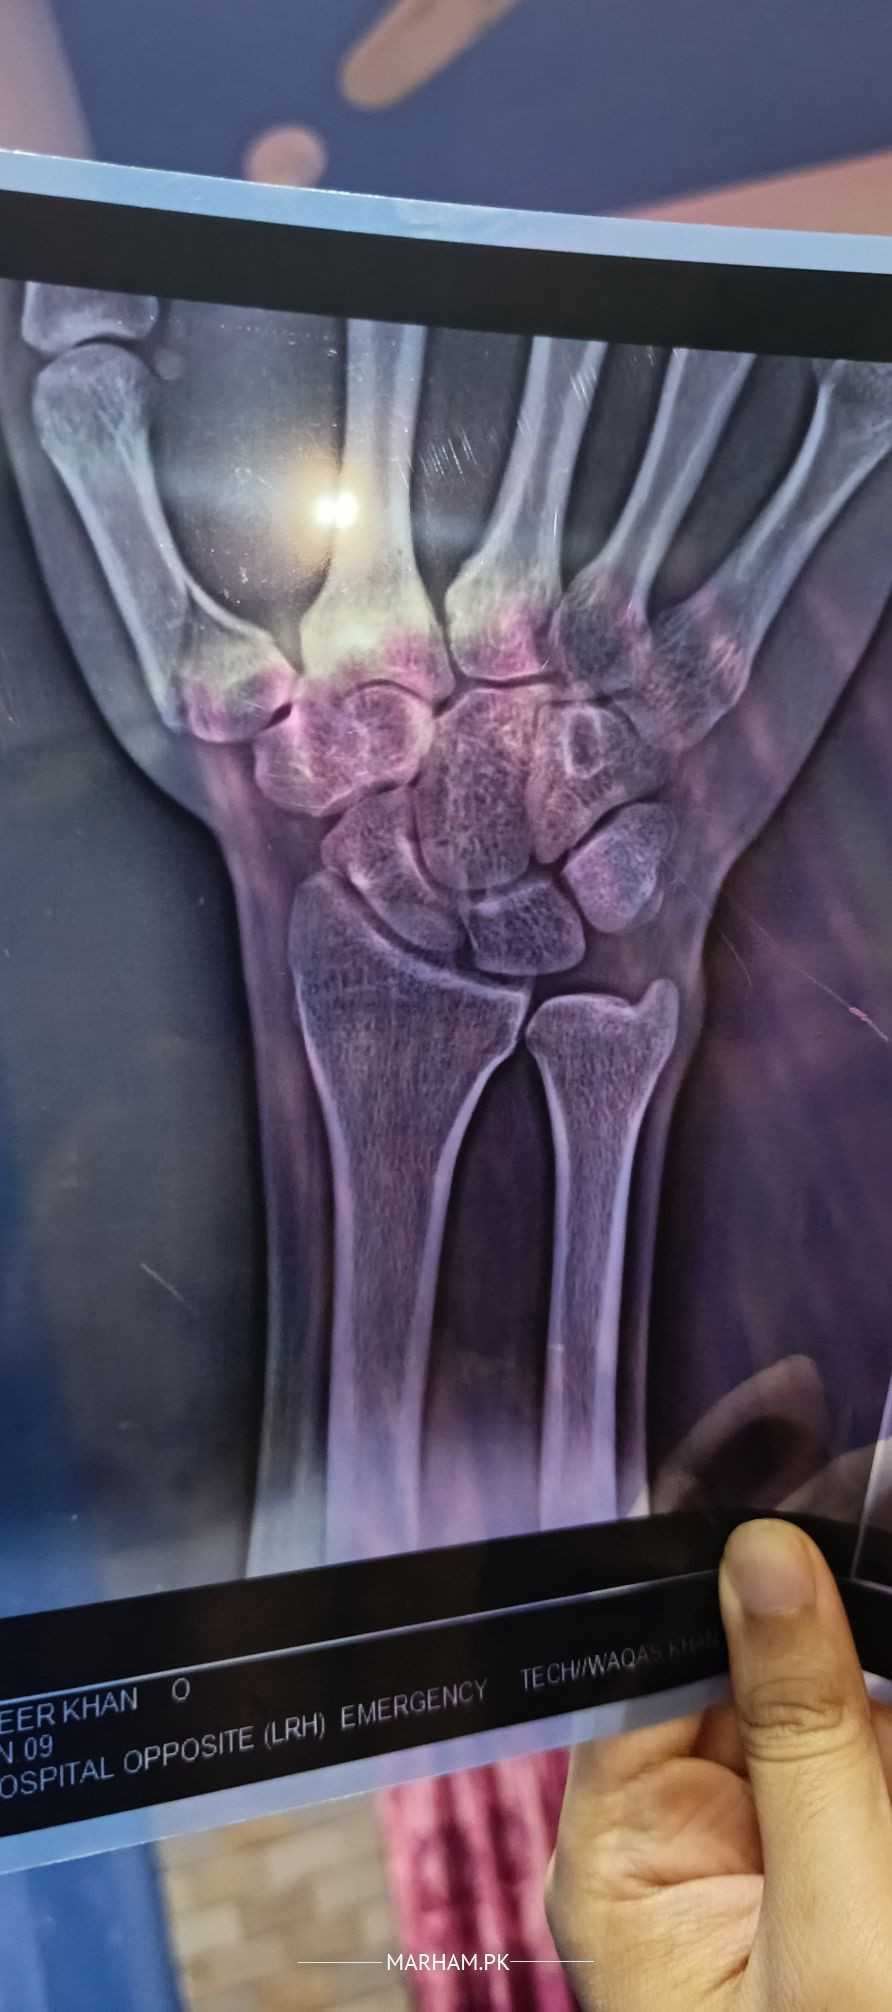

assalam u alaikum mera thumb fracture hoa tha 3 weeks tak mene plaster of paris lagwaya per kal remove karwa deya fracture tora theek hoa hai tora baqi hai Xrays attach kardi hai.regnamai karde please

please keep it in bandage to protect from accidental injury again. Start Physiotherapy to regain range of movements slowly and gradually. 3 to 4 weeks are sufficient for initial immobilization.

still you are feeling pain at fracture site then continue splint for two week more

3 weeks are sufficient, pain ,if any, will be due to immobilization. Please protect it especially if it is your right hand POP for more than 4 weeks will serve no good.

if you have done POP keep it for maximum 7 to10 days, then remove and go for Physiotherapy.